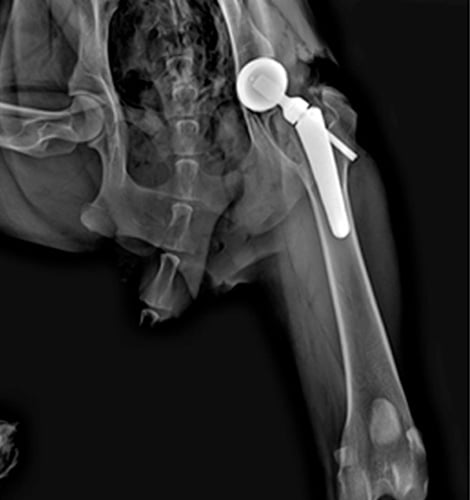

인공고관절 치환술은 골반의 관골구부분과 대퇴골의 머리부분을 인공 이식물로 대체하는 수술방법입니다.

흔히 고관절 이형성, 고관절 탈구, 골절, 퇴행성 관절염 등으로 인해 걷기 힘들고, 통증이 심하거나 일상생활이 어려운 경우 가장 최선의 선택이 THR (인공 고관절 치환술)입니다.

기존의 FHNO(대퇴골두목 절제술) (왼쪽사진)과 비교하여 THR(인공 고관절 치환술은)은 해부학적구조와 기능을 회복시켜,

정상에 가까운 보행과 활동성을 기대할 수 있으며 재활의 필요성도 적고, 대형견에서도 좋은 결과를 얻을 수 있습니다.